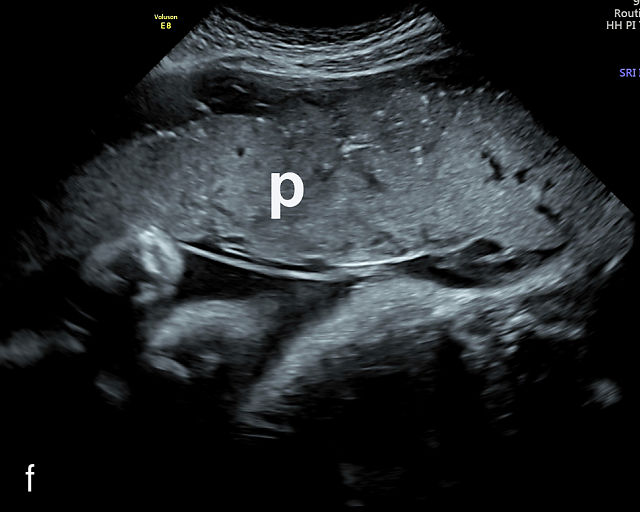

In the early first trimester, trophoblastic tissue appears as an echogenic ring encircling the gestational sac (Figure 1a). By the late first trimester, the placenta becomes recognizable as a distinct structure on ultrasound (Figure 1b). Initially, it presents as a homogeneous echogenic mass (Figure 1b–d) but undergoes progressive differentiation, becoming more heterogeneous as pregnancy advances from the second to third trimester (Figure 1e–g). By the third trimester, cotyledons become discernible, and in the late third trimester, calcifications frequently appear basally and around the cotyledons (Figure 1g).

1

Ultrasound images of development of the placenta (P/p). (a) Trophoblastic tissue appearing as an echogenic ring surrounding the gestational sac at 6 weeks' gestation. (b) Placenta at 12 weeks has become a discrete, uniformly echogenic mass. (c) Placenta at 17 weeks. (d) Placenta at 20 weeks. (e) Placenta at 27 weeks. (f) Placenta at 33 weeks. Increasingly, differentiation and heterogeneous appearance is seen, with demarcation of the cotyledons. Basal calcifications are beginning to appear. (g) Placenta at 40 weeks, showing a distinctly heterogeneous appearance, with clear demarcation of the cotyledons and presence of calcifications.